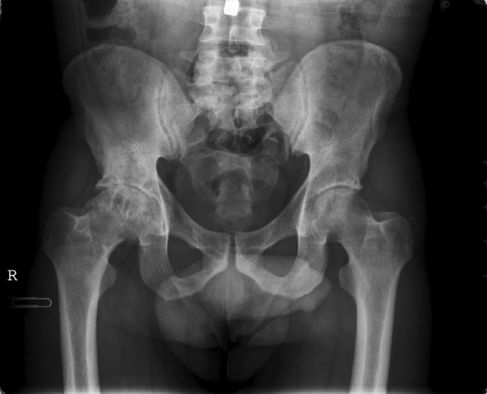

Coxartrosis

ARTROSIS DE CADERA - COXARTROSIS

La Artrosis es una enfermedad degenerativa de las articulaciones. Consiste en la pérdida del cartílago articular, la formación de osteofitos y la deformación de la articulación afectada. Existen factores desencadenantes, como un traumatismo importante, y factores que aceleran la progresión de la artrosis, como la inestabilidad o la sobrecarga mecánica de la articulación. También existe una predisposición genética a padecer la enfermedad. La artrosis es habitual en articulaciones como la rodilla, la cadera, las articulaciones de las manos y la columna vertebral.